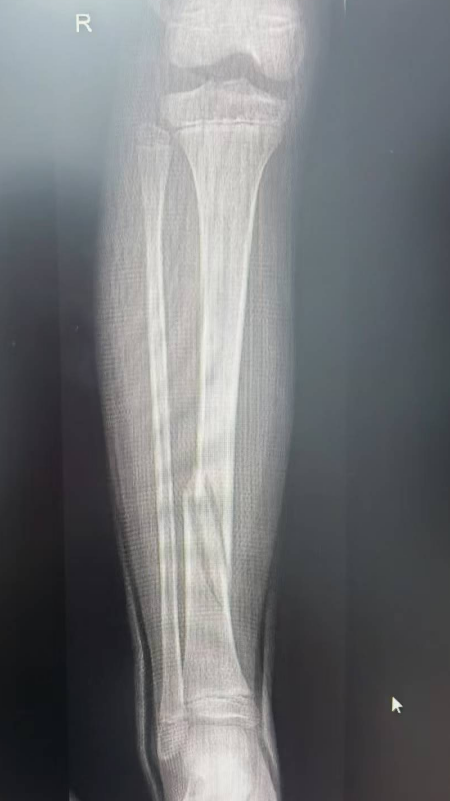

如5岁男童瑞瑞踩着平衡车从广场边缘台阶上摔下,导致左臂肱骨髁上骨折;6岁女童萱萱骑滑板车避让障碍物失去平衡,重重摔倒,造成胫骨骨折。

桡骨远端骨折,通过手法复位